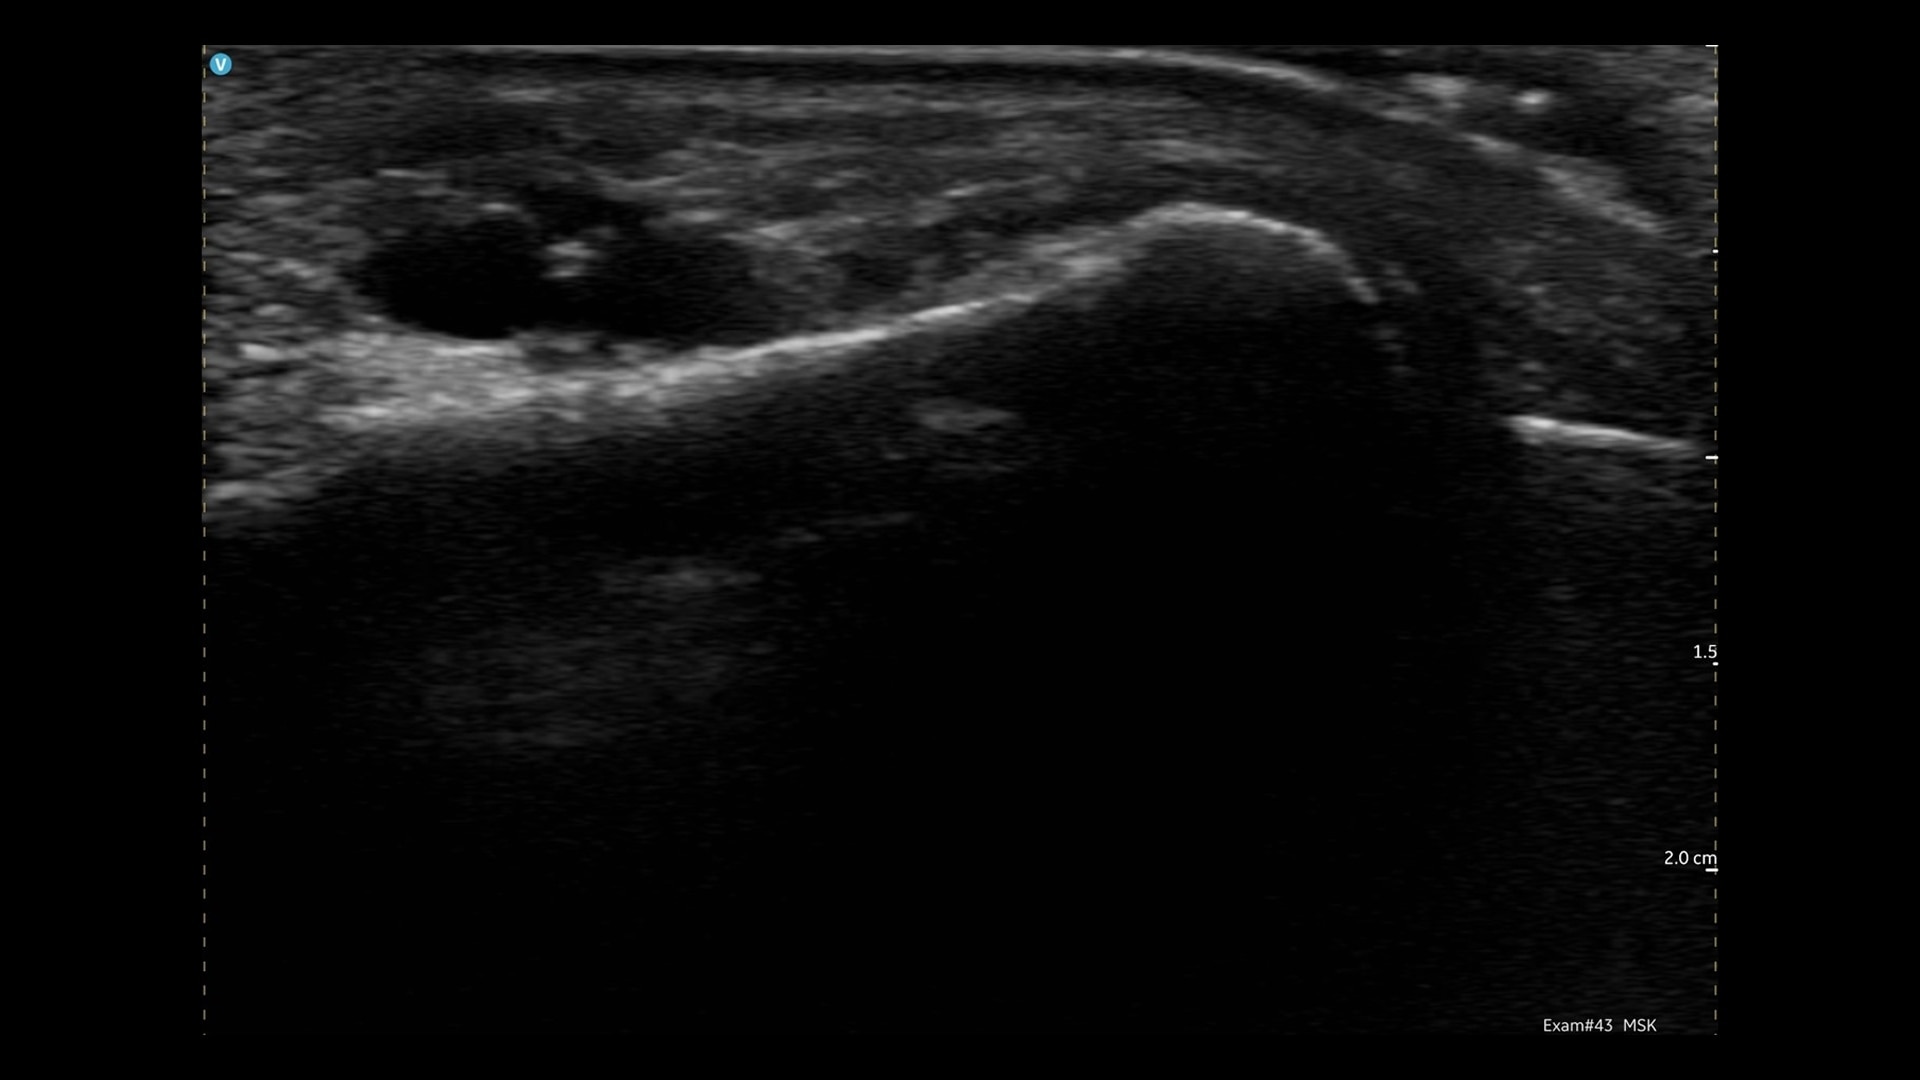

On-the-spot diagnosis

Immediate ultrasound assessment of sports injuries, crucial for quick decision-making.

Crystal-clear Images

Wireless, crystal-clear imaging at your fingertips - wherever you need it.

Diagnostic confidence

Visualizing internal structures in real-time can enhance clinician’s confidence.